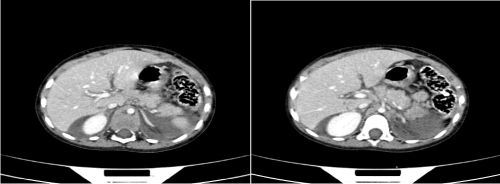

The second patient had a full thickness laceration involving the tail of the pancreas (Figure 2). In addition, he had multiple liver, involving segments 6 & 7 as well as the caudate lobe and splenic lacerations (Figure 3). The splenic vessels seemed intact.

Figure 2. Laceration involving the tail of the pancreas

Figure 3. Splenic and liver lacerations